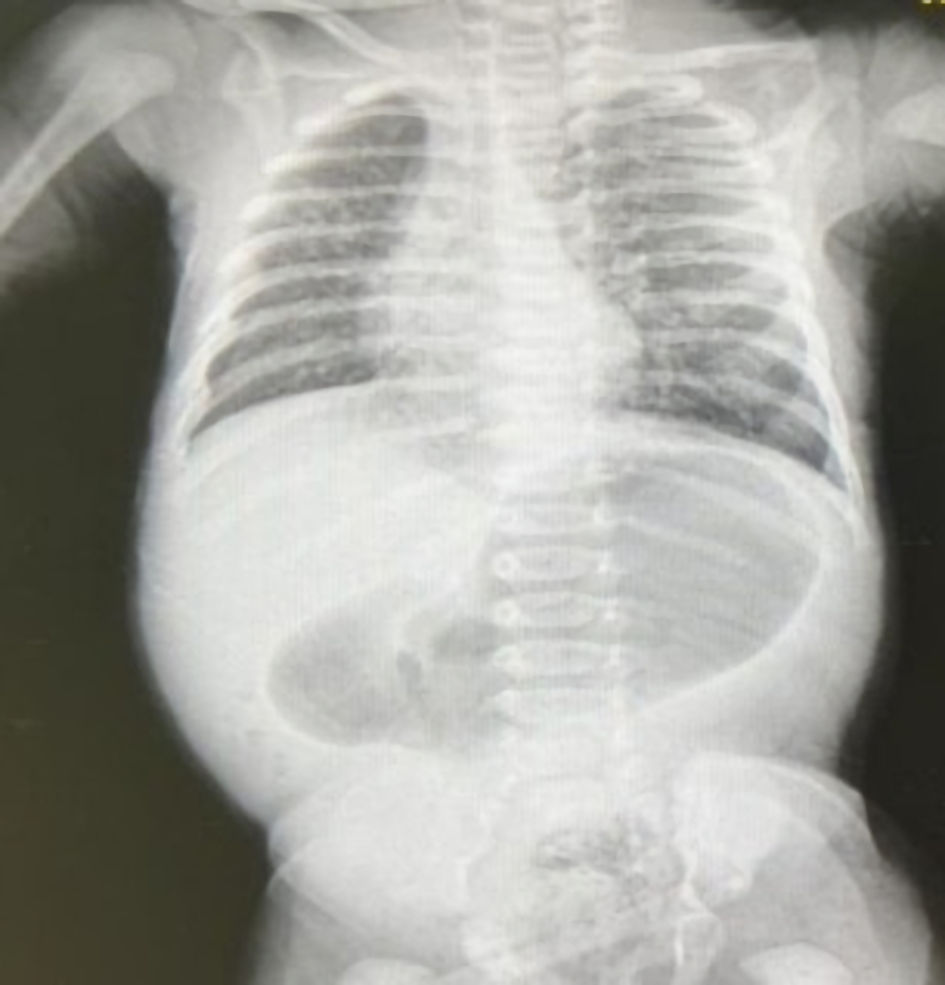

An abdominal X-ray demonstrated a single large bubble (Fig. 2), prompting an urgent surgical consultation. Laboratory results confirmed severe dehydration, with elevated creatinine and urea levels, coagulopathy characterized by a significantly elevated international normalized ratio (INR), and elevated lactate levels with a metabolic alkalosis on venous blood gas, all suggestive of hypoperfusion and systemic compromise.

Figure 2. An abdominal X-ray demonstrated a single large bubble.